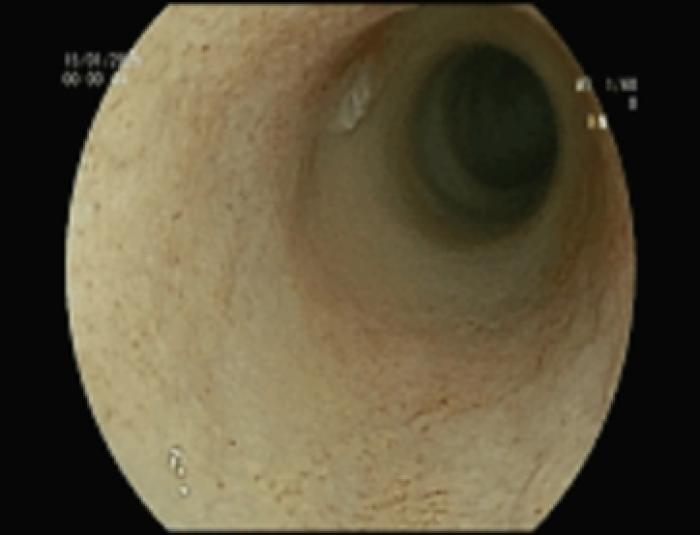

- Colitis e ileítis congestiva ligera (Figura 5)

Después de 15 días se realiza esofago-gastro-duodenoscopia, colonoscopia e ileoscopia para realizar biopsias, obteniendo los siguientes resultados:

- Gastritis congestiva ligera (Figura 12)

- Duodenitis congestiva y erosiva moderada (Figura 13)